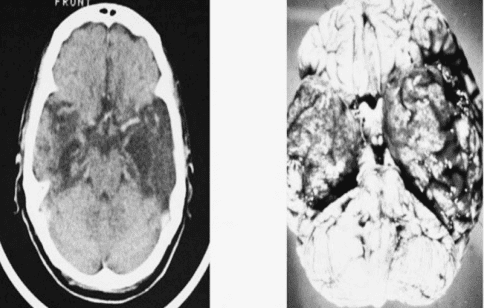

Khi nhắc đến viêm não thường được hiểu là viêm não do virus gây nên. Viêm não do HSV là bệnh lý nhiễm trùng thần kinh trung ương cấp tính, xuất hiện tản phát, không theo mùa. HSV xâm nhập nhu mô não, gây hoại tử kèm xuất huyết não.

Viêm não do HSV thường khởi phát nhanh, cấp tính, tỷ lệ tử vong cao. Triệu chứng biểu hiện như sốt, rối loạn ý thức, diễn biến nặng. Nếu được phát hiện sớm, điều trị đặc hiệu kịp thời, chăm sóc tích cực, người bệnh có tiên lượng tốt hơn.